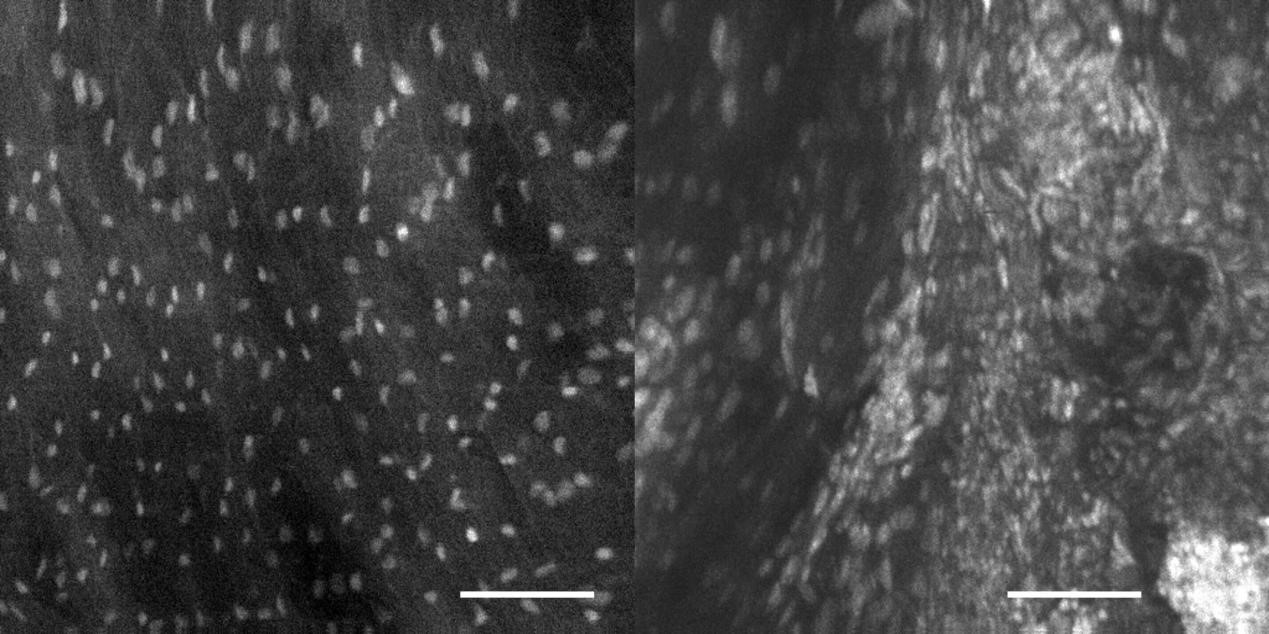

2、宮頸癌OptiScan成像

左:正常鱗狀上皮;右:宮頸上皮肉瘤變。

注:0.05%吖啶黃溶液外用。Scale bar=100μm。